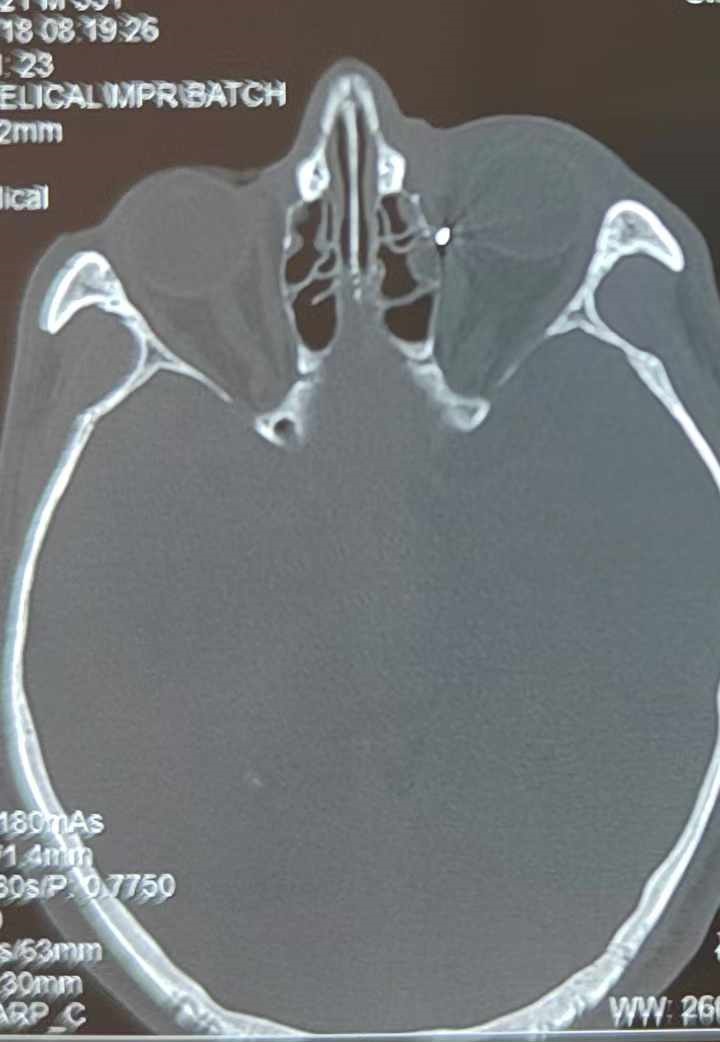

從CT報告中可以看出,高先生眼內(nèi)的異物不是很大,但位于眼窩深處,緊鄰鼻骨,從CT影像判斷應(yīng)該是金屬或合金異物。一般臨床上遇到這樣的情況,醫(yī)生會建議“保守觀察”,若異物傷及神經(jīng)、發(fā)生炎癥感染等,則需到條件較好、有眼眶病和眼外傷專業(yè)醫(yī)師的醫(yī)院進行二期眶內(nèi)異物取出術(shù)(2021年《中國眼眶異物診斷和治療專家共識》)。

李海波博士介紹,眶內(nèi)異物想要通過手術(shù)取出,難度很大,一是因為位置隱匿,無法實現(xiàn)可視化操作;二是如果是磁性異物,現(xiàn)有手術(shù)工具磁性強度有限,很難吸出這么深的異物;三是可操作空間極為狹小,眶周軟組織多,異物周邊包裹緊密,像高先生這種情況,異物周邊還有很多神經(jīng)、血管,手術(shù)難度更高。